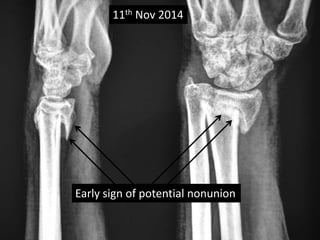

Case three

• 40 years old Female,

• Sustained fracture lower end radius on 13th Sept

2014.

• Received no treatment.

• No co-morbidity.

• Chief complaint was deformity of wrist.

• X-rays on 11th Nov 2014 showing delayed union

• Clinically no disability.

• Patient refused corrective surgery.

11th Nov 2014

Early sign of potential nonunion

11th Nov 2014 Early sign of potential nonunion